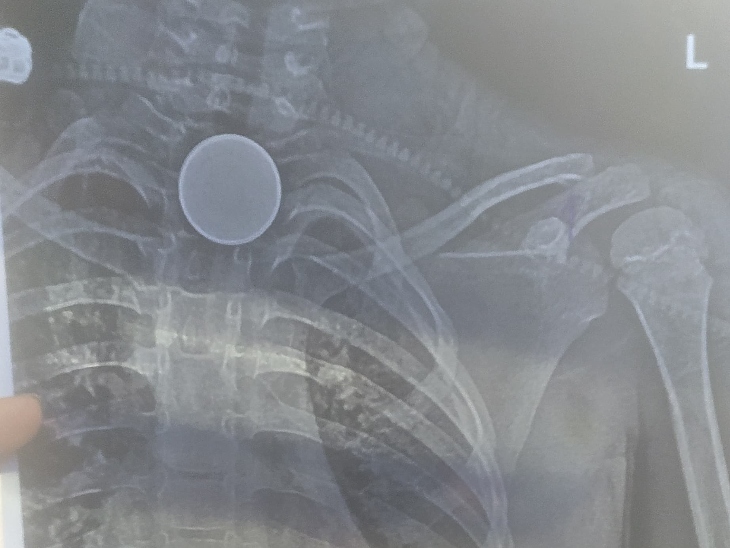

कोरबा: जिले में 8 साल के मासूम के सीने में सिक्का फंसने से उसकी मौत हो गई। शिवम सारथी ने सिक्का कब और कैसे निगला इसकी जानकारी परिजनों को भी नहीं थी। जब तबीयत बिगड़ी तब वे जिला अस्पताल लेकर पहुंचे। जहां एक्स-रे रिपोर्ट में सिक्के के फंसने की पुष्टि हुई।

शुक्रवार (31 अक्टूबर) रात अचानक शिवम की तबीयत बिगड़ने लगी। उसके हाथ-पैर ठंडे पड़ने लगे और सांस लेने में दिक्कत होने लगी। परिजन उसे तत्काल जिला मेडिकल कॉलेज अस्पताल लेकर पहुंचे। डॉक्टरों ने एक्स-रे रिपोर्ट के आधार पर बताया कि शिवम के सीने में सिक्का फंसा है, जिससे उसे सांस लेने में परेशानी हो रही है।

वहीं जिला मेडिकल कॉलेज के सह अधीक्षक रविकांत जाटवर ने बताया कि रात 12 बजे एक्सीडेंटल मामला सामने आया था। जहां सांस लेने में दिक्कत हो रही थी। बच्चे की हालत गंभीर थी। इलाज किया जा रहा था। एक्स-रे में सिक्का नुमा चीज दिख रही है, लेकिन पोस्टमॉर्टम का दौरान सिक्का नहीं मिला है।

एक्स-रे रिपोर्ट में सीने में सिक्के के फंसने की पुष्टि हुई थी।